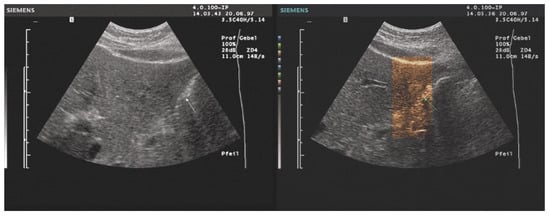

Assessment of Hypertension in Hemodialysis Patients with the Concomitant Use of Peridialytic and Interdialytic Ambulatory Blood Pressure Measurements